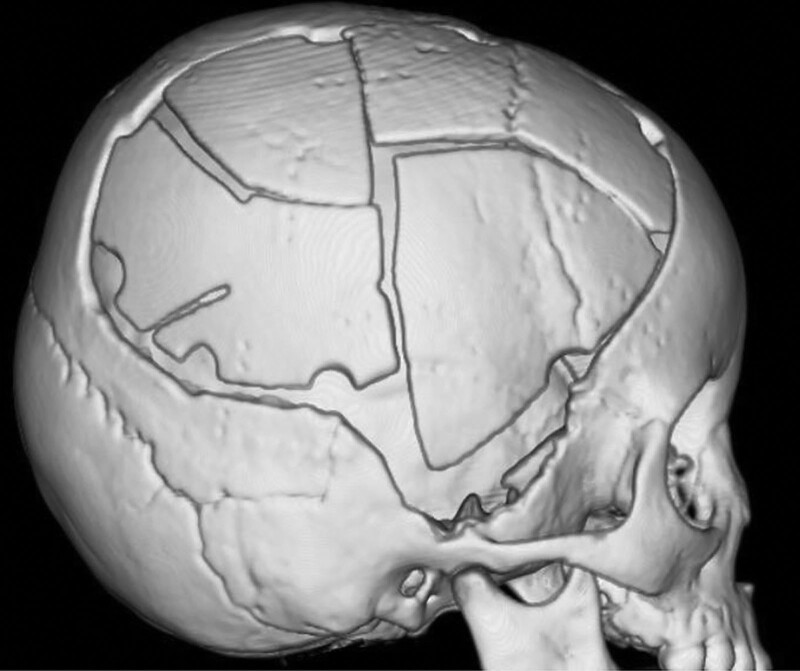

لعلاج النزف داخل الجمجمة، غالبًا ما يتم إجراء عملية استئصال القحف لتخفيف الضغط. لتقليل الضغط داخل الجمجمة، تتم إزالة سديلة عظم الجمجمة. تتم إعادة بناء العيب العظمي باستخدام عظم ذاتي المنشأ أو مادة صناعية بعد تحسن الوذمة الدماغية. وفي حالات الأطفال، قد لا تتناسب المادة الاصطناعية مع نمو الجمجمة، مما يؤدي إلى ظهور فجوات ونتوءات. عيب آخر هو أن العظم الاصطناعي عرضة للعدوى. على العكس من ذلك، ينمو العظم ذاتي المنشأ استجابة لنمو العظام المحيطة ويكون لديه خطر ضئيل للإصابة بالعدوى. إذا تم استخدام عظم ذاتي المنشأ، فيجب الحفاظ عليه حتى عملية رأب القحف.